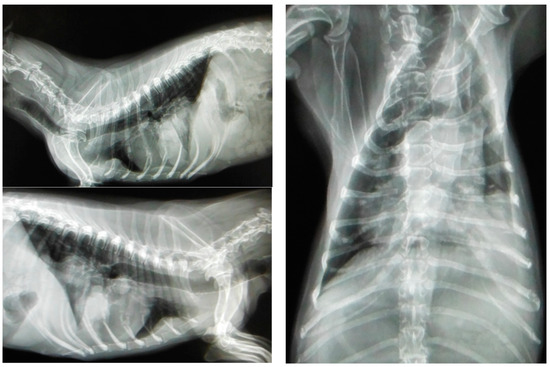

Most canines with mammary tumors are clinically healthy at the time of diagnosis [130]. However, patients with metastasis can present fatigue, lethargy, weight loss, dyspnea, cough, edema or lameness. Clinical signs depend on the extension and localization of metastasis [24,52]. Approximately 50% of mammary carcinomas metastasize to regional lymph nodes. Lymph node involvement is variable and can promote distant metastasis, most frequently to the lung (see Figure 3); metastatic bone lesions may also occur [24,52,131].

Figure 3.

Three projections of thoracic radiographs, right and left lateral and ventrodorsal, with nodular interstitial pattern in a 12-year-old Dachshund patient with metastatic mammary carcinoma (own photo).

Lungs are the most common site of metastasis in mammary tumors; therefore, radiographic studies of the chest in its three projections (Li-Ld, Ld-Li and VD) are essential to evaluate the presence of metastasis in the lungs. Other less frequent sites of metastasis are the liver, bone, brain, spleen, kidney, adrenal gland, uterus, heart, muscle and pancreas. Additional studies such as abdominal ultrasound, bone X-rays or CT scans are necessary to assess these possible scenarios [61,135].